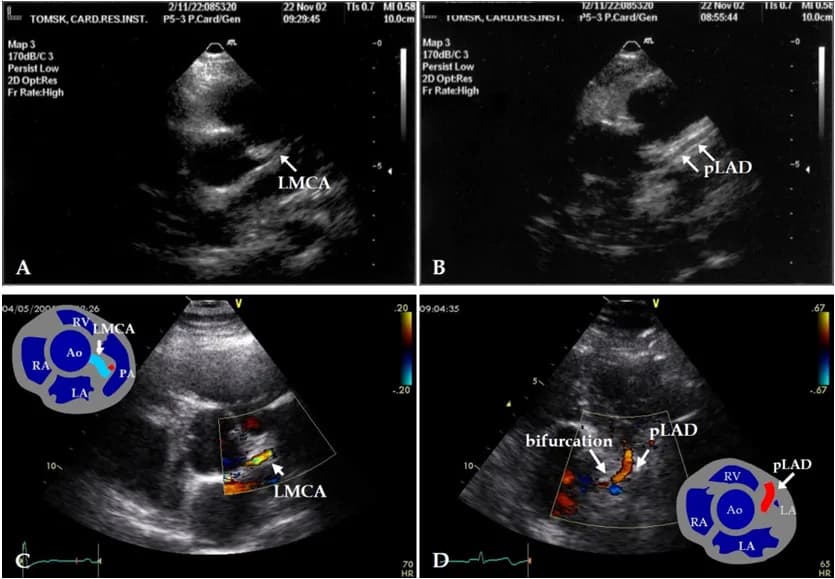

siêu âm timsiêu âm Dopplerhẹp van động mạch chủbệnh van động mạch chủhở van động mạch chủ

Vai trò siêu âm tim trong chẩn đoán bệnh van động mạch chủ

Siêu âm tim trong chẩn đoán bệnh van động mạch chủ

1. Siêu âm tim

Định nghĩa: Siêu âm tim là một phương pháp thăm dò ch...